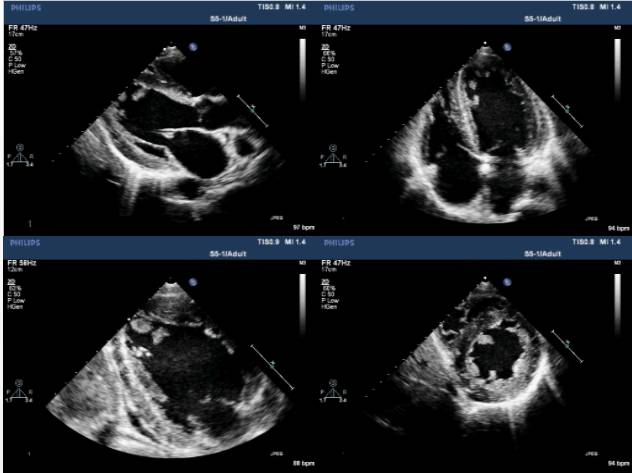

2016-11-23心超:

◆左房增大(46mm),左室增大(LVEDD 60mm),

◆左室壁整体收缩活动减弱(左室壁均匀性增厚,心肌内回声不均,LVEF 38%),

◆左室舒张功能减退 E/E`>12;

◆左室内多发占位(下壁心尖部2处、侧壁心尖部1处团块样中等回声,随血流甩动,有蒂连接室壁,大小分别为19*14mm、15*9mm、8*4mm);

◆右房增大(52*44mm),右室内径正常,TAPSE 16mm;

◆微量心包积液(左室后方房室沟内4mm无回声区)